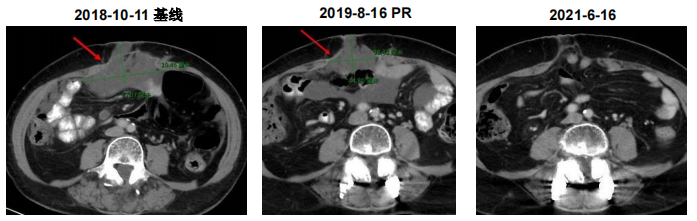

李健教授分享了一例他印象非常深刻的老年患者,他谈到:“我们中心入组的病例中有不少偏老年的患者,我印象深刻的患者是其中一位76岁女性,她2013年因‘乏力纳差伴贫血(HGB=60g/L)’就诊,2013年7月17日在外院诊断为结肠癌、大网膜转移、不全性肠梗阻。她的治疗经过比较曲折,那时还缺乏免疫治疗的药物,因此她接受了术前新辅助化疗,当时疗效评估为疾病稳定(SD),随后患者行剖腹探查+横结肠癌根治切除手术,肿瘤病理分期为pT3N0(IIA期)。术后患者接受辅助化疗3周期,但是不久后相继出现了盆腔转移、脾转移、右侧髂窝转移。这也比较符合MSI-H患者的特点,这类患者普遍对化疗不敏感,容易出现腹盆腔、腹膜转移。而患者术后出现转移后,便一直在自行服用中药,未接受规范治疗。

由于符合入组条件,患者于2018年9月30日入组“恩沃利单抗单药治疗 dMMR/MSI-H 晚期结直肠癌及其他晚期实体瘤患者的临床疗效和安全性的多中心 II 期临床研究”。于2018年11月5日起开始皮下注射恩沃利单抗150mg(d1、8、15、22,q28d),治疗至2021年8月4日。治疗期间无严重不良反应,患者病灶较治疗前显著缩小,达到完全缓解(CR),提示恩沃利单抗具有较好的疗效。”

患者CT结果